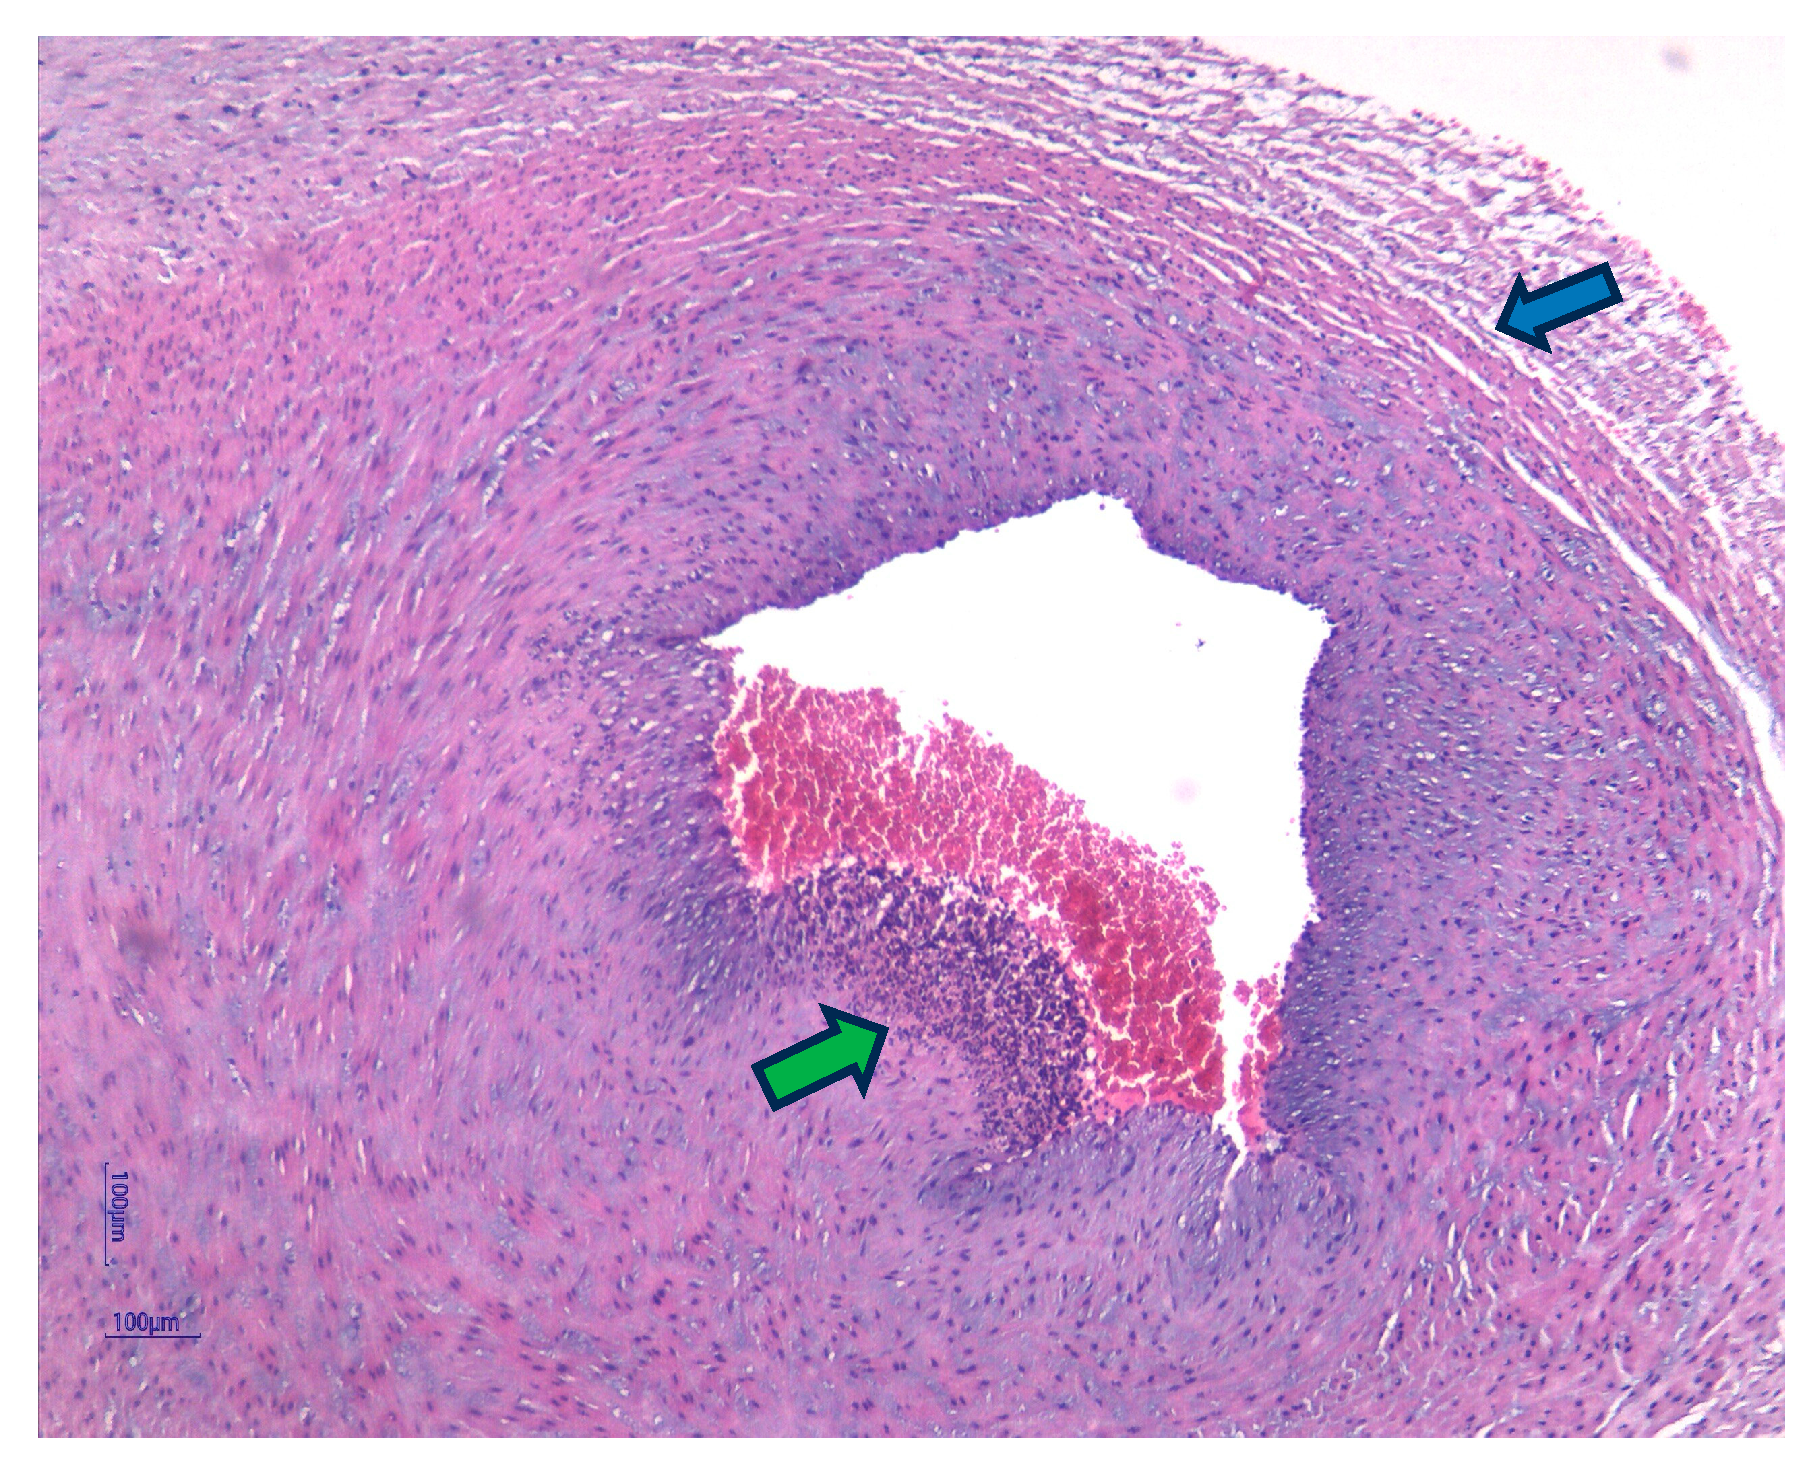

- Pacora, P.; Chaiworapongsa, T.; Maymon, E.; Kim, Y.M.; Gomez, R.; Yoon, B.H.; Ghezzi, F.; Berry, S.M.; Qureshi, F.; Jacques, S.M.; et al. Funisitis and chorionic vasculitis: The histological counterpart of the fetal inflammatory response syndrome. J. Matern. Neonatal Med. 2002, 11, 18–25. [Google Scholar] [CrossRef]

- Kim, C.J.; Romero, R.; Chaemsaithong, P.; Chaiyasit, N.; Yoon, B.H.; Kim, Y.M. Acute chorioamnionitis and funisitis: Definition, pathologic features, and clinical significance. Am. J. Obstet. Gynecol. 2015, 213 (Suppl. 4), S29–S52. [Google Scholar] [CrossRef] [PubMed]

| Funisitis (n = 37) | 33 (89.2%) | 4 (10.8%) | 0.001 | |